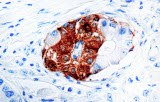

CE/IVD antibodies for immunohistochemistry (IHC) in neuropathology are validated in vitro diagnostic reagents used to detect specific neuronal and glial antigens in formalin-fixed paraffin-embedded (FFPE) tissue. Peer-reviewed neuropathology literature supports their role in improving reproducibility and diagnostic accuracy in central nervous system (CNS) diseases, including brain tumors and neurodegenerative disorders.

Targeted proteins such as GFAP, OLIG2, NeuN, synaptophysin, neurofilament, and Iba1 reflect astrocytic, oligodendroglial, neuronal, and microglial lineages. Their expression patterns are widely used in peer-reviewed studies to define CNS cell identity, differentiation state, and neuroinflammatory or degenerative processes.

CE/IVD IHC antibodies support CNS tumor classification (gliomas, embryonal tumors, metastases), assist in differential diagnosis, and help identify proteinopathies associated with Alzheimer’s disease and other neurodegenerative conditions. They are routinely used in biomarker panels for tumor grading and diagnostic stratification in neuro-oncology.